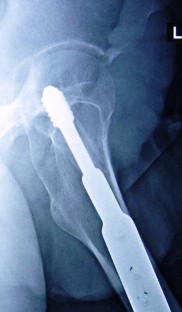

Dynamic hip screw and fibular strut graft for fixation of fresh femoral neck fracture with posterior comminution

Posterior comminution of the femoral neck fracture is a major cause of delayed and non-union owing to the loss of the buttressing effect against the posterior rotation. When a femoral neck fracture with posterior comminution is anatomically reduced, only the anterior portions of the femoral neck fracture surfaces are brought into contact leaving a posterior defect. The purpose of this study was to evaluate the use of fibular strut grafting and dynamic hip screw (DHS) for fresh femoral neck fractures with posterior comminution in young patient less than 50 years.

Between October 2012 and March 2016, 35 patients aged 20–50 years, 30 men and 5 women underwent fixation using DHS and fibular strut grafts for Garden grades III (25 patients) and IV (10 patients) femoral neck fractures with posterior comminution. All fractures were reduced by closed methods, and no hip was aspirated. Clinical and radiological outcomes were evaluated.

All patients were in the age group of 20–50 years (mean 37 years). The mean delay in presentation after injury was 1 day. The mean final follow-up for these 35 patients was 27.2 months. Healing of the femoral neck was attained in 34 cases, with an average time to union of 4.8 months (range 4–8 months). One patient underwent arthroplasty due to failure of fixation. According to the Harris hip score, outcome was good to excellent in 30 patients, fair in 4, and poor in 1.

In our study, only one patient developed non-union and no patients had avascular necrosis of the femoral head. Closed reduction, fibular strut grafts, and DHS fixation is a reliable procedure for femoral neck fractures with posterior comminution in young adults.

Fig. 3